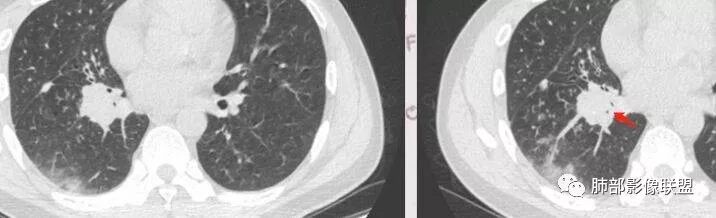

1.分布,你曾经说过一次,但是可能很多人没有听过,这边再次提出,就是如果是肺原发的,和支气管来的一个区别。这个我来找一下,稍后多说说。2.这个GGO到底是边界清楚还是不清楚。这个问题有一点主观,我觉得还蛮清楚,但是你说不清楚,有时候征象每个人把握不同,尤其是我们把握的可能会偏差,眼神不好。

3.我比较认同的是,确实可以看到很多树丫征,这个我也觉得结核无法排除的地方 。

4.有关于支气管,有扩张,但是也有地方是粗细不均,扩张支持淋巴瘤,但是粘液腺癌也无法排除。

5,我注意到你说中央间质增厚,还是想说支气管壁增厚呢?支气管壁好像是增厚的,这个可能是提示是气道来的。

吴倩南京市第一医院:第一个是分布的定位问题,南大把他分成三种,第一个肺实质肺泡来源的,第二个支气管从上面往下来的,第三个是间质来的。如图如果是肺泡本身发生的病变应该是外周大,实,往里面变小,变虚,还有支气管壁不增厚。

但是这个病例是由支气管往下,越来越淡,与支气管是平行走形,然后支气管壁增厚,还有树丫,虽然带着GGO的,分布属于支气管往下来的,这个和粘液腺癌不同,和肺炎链球菌也不同。比较符合TB,支原体这些。

有树芽征,树芽征一般提示小气道受到影像,是炎性病变的特点。周围很多磨玻璃影,一般提示炎性病变,考虑急性为主,最起码有急性病变在其中。但该病人存在一个问题,其前基底段支气管有扩张,周围有实变,考虑原有病灶,有支气管扩张一般不考虑恶性肿瘤,肯定是慢性炎性病变。

中央间质的增厚和支气管壁增厚的问题,支气管壁其实它不是中央间质,支气管血管束、支气管周围的那些间质成分才是中央间质。它们的差异,中央间质是围绕血管、支气管周围,但支气管壁增厚是以支气管为主。我们一般来说横切面切到了紧隔的支气管、血管,除非它本身把支气管扩张独立出来,发现支气管周围壁的增厚程度和血管不对称。一般支气管、肺动脉伴行时大小是差不多的,发现支气管的周围外径明显大于血管外径,此时我们考虑支气管来源。支气管和血管束横切面时联系很紧密,周围一圈在一起,大小形态差不多,那就考虑中央间质来源的。前面分析的结节病分布特点如上,没有偏侧性。血管炎往往血管束增粗,比支气管厉害一些,当然也不是绝对的,大部分是这样的。